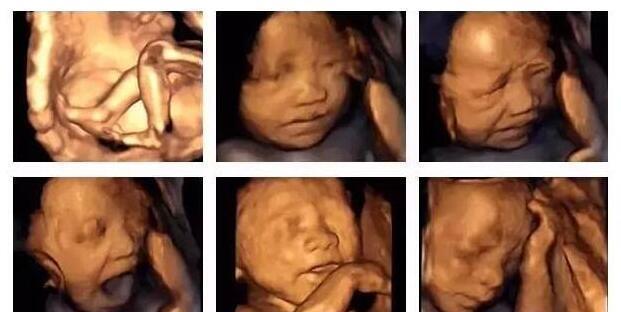

四维彩超的检查时间是孕22-28周,此时的胎儿还没有足月,小小的一只,浑身皱巴巴的,还没有发育完全;同时胎儿的身上还有一层厚厚的胎脂,这些胎脂让胎儿的皮肤看起来凹凸不平,拍摄的时候,自然会影响到照片,让胎儿的鼻子嘴巴看起来特别大。

不要担心,胎儿在孕晚期的发育中,胎脂会慢慢脱落一些,皮下脂肪快速的囤积,胎儿会越来越丰满,五官也会越来越好看。就拿新生儿来说,宝宝刚出生的时候,皱巴巴的像个没毛的猴子,丑得要命,但是过了三四十天,宝宝长大一些,会变得白白胖胖特别可爱。

最后,胎儿四维彩超的照片,鼻子大嘴巴大,看起来特别丑 ,都是正常的,只要检查胎儿发育正常,没有畸形就好。至于孩子的长相问题,还得看父母的基因遗传,父母颜值高,孩子的颜值也不会太低;如果父母颜值太低,那就不能怪孩子长得不可爱了,只是随了父母而已。